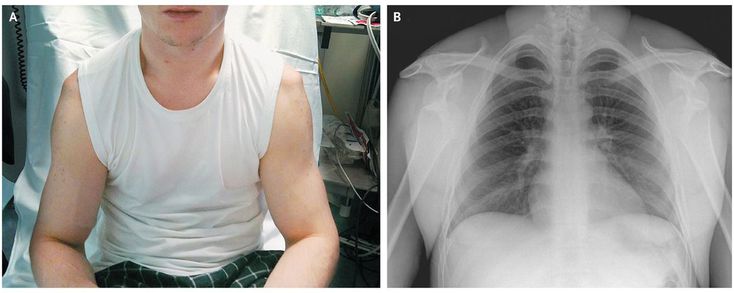

A 34-year-old man with a history of recurrent dislocations of both shoulders presented with sudden excruciating pain in both arms and an inability to move either of them, after attempting to lift a weight equal to his body weight above his head in the gym. On physical examination, the patient was unable to move either shoulder, and squaring of the normal shoulder contour was observed bilaterally (Panel A). Radiographs showed the anterior and inferior positions of the humeral head relative to the glenoid fossa (Panel B). The patient received a diagnosis of bilateral anterior shoulder dislocation. After the patient received morphine for pain relief, the shoulder dislocations were reduced individually with the use of gentle external rotation. Anterior shoulder dislocation accounts for the majority of joint dislocations seen in the emergency department. The diagnosis of dislocation is based on a number of factors, including pain and range of movement of the afflicted joint. Asymmetry of the joint typically heralds a dislocation. When bilateral dislocation occurs, this clinical asymmetry is absent, so attention must be paid to the clinical history and physical findings.